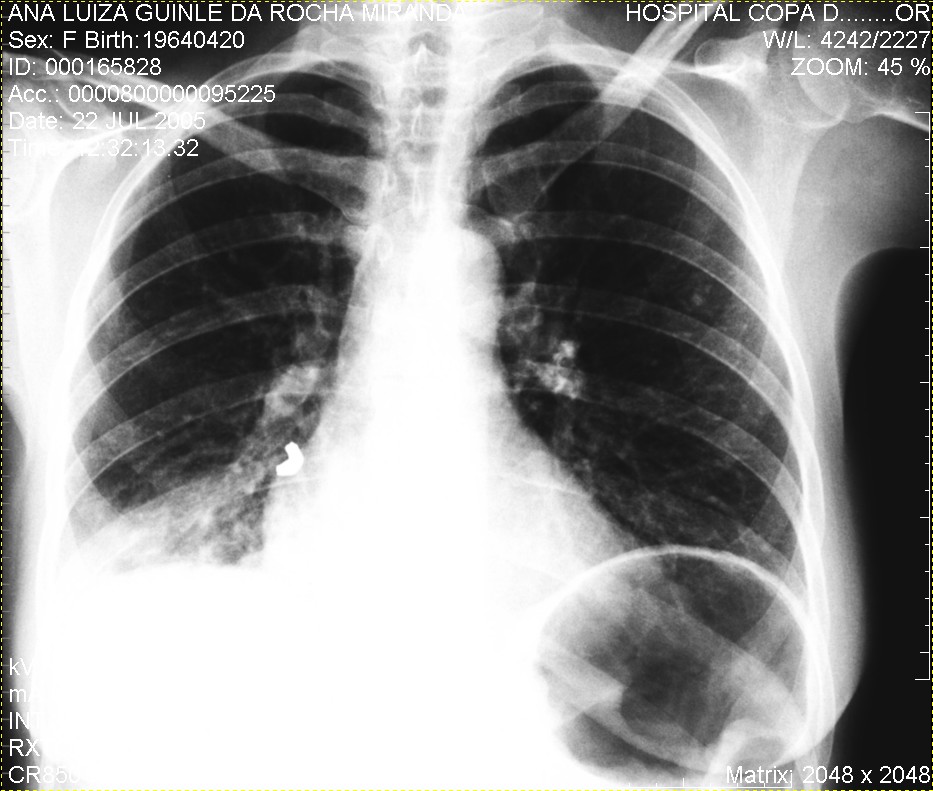

Caso Número 4/2018: “Uma sessão interativa de casos em radiologia torácica – Parte 1”

Caso relatado na Reunião de Discussão de Casos Clínicos do Hospital Universitário Prof. Polydoro Ernani de São Thiago, iniciada pelos Profs. Jorge Dias de Matos, Marisa Helena César Coral e Rosemeri Maurici da Silva, em julho de 2017. No dia 14 de junho de 2018, no auditório do HUPEST, realizou-se a apresentação e discussão do caso cujo registro é apresentado a seguir. Trata-se da discussão de onze casos em radiologia torácia, de forma interativa com a plateia, e assim ocorre também neste artigo.